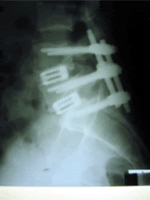

przypadkiem nie chodź do kręgarza czy jak tam zwał bo Cie moze sparaliżować do końca, umnie skonczyło sie to tak:

http://i173.photobucket.com/...48/mcslavko/20b.gif

http://s173.photobucket.com/...ent=20120722136.jpg

http://i173.photobucket.com/...28.jpg?t=1341652604Powered by 4x4 - pieknie pieknie , juzek 14/10/12 07:47

Mozesz opisac jak to u Ciebie wygladalo? Jakie objawy byly, jak sie teraz czujesz, ile czasu po operacji itd..?- ból prawej ręki, całego ramienia... , McSlavko 14/10/12 12:45

a do tego mi jakieś mrówki latały po prawej nodze (?) skonczyło sie jak widać, operacja była 5 lipca, teraz teoretycznie ból ręki minał, ale zaczeła boleć szyja, jazda samochodem to katorga... spanie, dłuższe spacery są męczarnią, juz sam nie wiem który stan był lepszy.Powered by 4x4